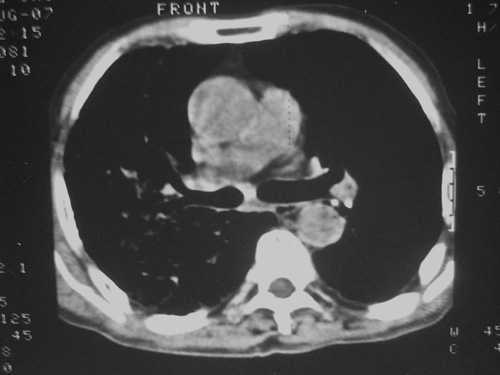

矽肺合并右肺结核可能性大.右侧少量胸腔积液.